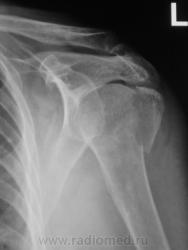

Пол пациента: Мужской пол Тип патологии: Травма Область исследования: Скелетно-мышечная система Методы исследования: Rg Травма. Пациент направлен на рентгенографию плечевого сустава. https://radiomed.ru/sites/default/files/styles/case_slider_image/public/user/12/2.p2070007.jpg?itok=vWEqKFRV ID:11857 Втр, 08/02/2011 - 21:33 #1 Глазков Игорь А... Не на сайте Был на сайте: 9 месяцев 2 недели назад Зарегистрирован: 19.12.2008 - 20:41 Публикации: 1597 головки плечевой кости в проекции хирургической шейки с отрывом большого бугра. Прийди к Себе

головки плечевой кости в проекции хирургической шейки с отрывом большого бугра.